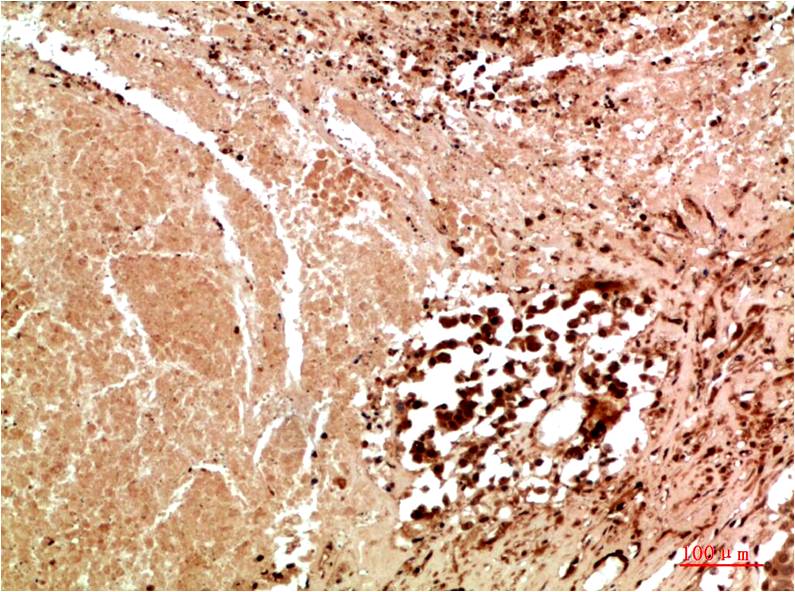

JNK3 Rabbit Polyclonal Antibody

Catalog NO.:BE3676

Applications :IHC

Recommended dilutions: IHC: 1:100-200

Specificity: The JNK3 Rabbit Polyclonal Antibody can detects endogenous JNK3 proteins.